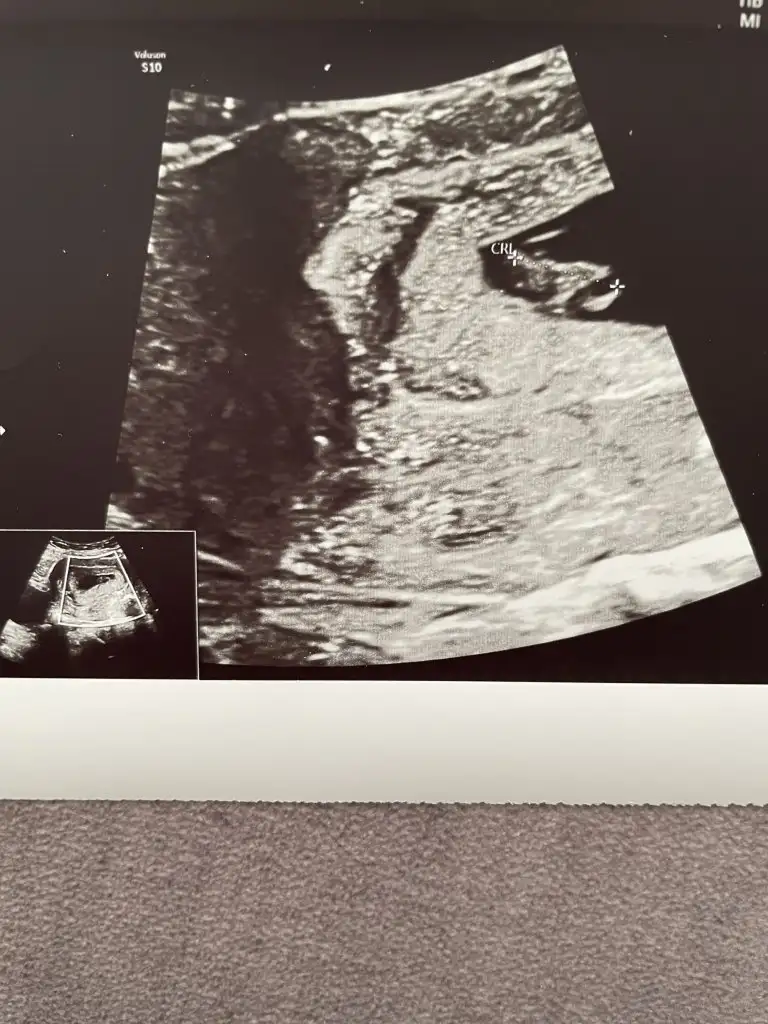

Kız gibi cinsiyet belli oldu mu canımBenim için de tahminde bulunur musunuz?

Ben de kıza benzettim cinsiyet belli oldu mu6+3 karından kuzumayy bakayım ne çıkacak

Doktorda kıza benziyor dedi bakalm daha kesin değil ama :)Ben kıza benzettim çünkü plesanta sağda